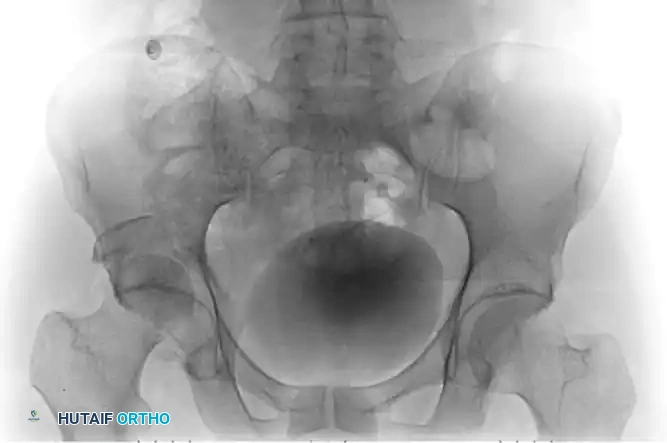

Figure 55-61A: Preoperative radiograph demonstrating a complex Pipkin IV fracture (posterior wall acetabular fracture with an associated femoral head fracture).

Figure 55-61B: Postoperative radiograph following surgical dislocation of the hip, open reduction and internal fixation of the posterior wall acetabular fracture, and débridement of the infrafoveal femoral head fracture.

Figure 55-61E: Postoperative AP pelvic radiograph showing the final construct.